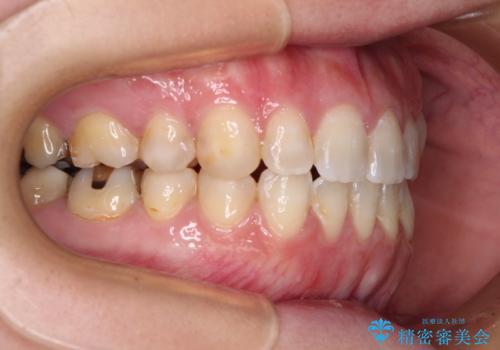

- 左上の八重歯と前歯のデコボコを気にして来院された患者様です。

下顎が左側にズレており、下顎前歯は1歯欠損していたため、左上小臼歯1本を抜歯し、ワイヤー装置にて矯正治療を行うこととしました。

骨格のズレと歯の欠損があったため、仕上がりの調整に時間がかかると思いましたが、舌突出癖の改善や顎間ゴムの装着をしっかりと行ってくださったので、速やかに治療を終えることができました。